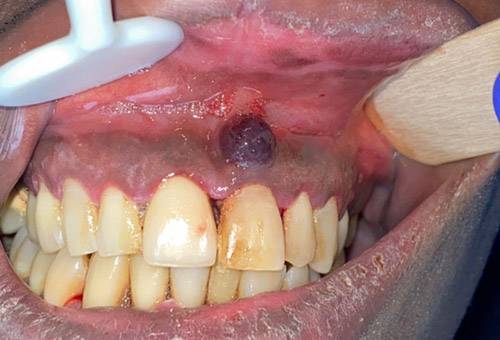

성(性)에 대한 인식이 갈수록 개방적으로 바뀌면서 파트너 수가 늘어나고, 성병 확산 위험도 높아지고 있다. 이때 주의해야 할 것이 에이즈로 이어지는 HIV(사람면역결핍바이러스) 감염인데, HIV 감염 증상이 입속에 나타날 수 있어 알아두는 게 좋다. HIV에 감염되면 '카포시육종'이라는 악성 종양이 생길 수 있는데, 일부는 입안 점막으로 증상이 발현된다. 프랑스 파리 파리시테대학교 피티에살페트리에르병원 치과 의료진이 HIV 감염으로 인해 입안 점막에 카포시육종이 나타난 사례 두 건을 보고했다.

피티에살페트리에르병원 치과 의료진은 "카포시육종은 1872년 처음 보고된 질병으로, HIV 감염 환자에게서 발생했을 때 이미 '에이즈 정의 질환'으로 간주된다"며 "남성과 성관계를 갖는 젊은 남성에게 가장 흔히 나타난다"고 했다. 이어 "붉은색이나 보라색 반점으로 나타나는 경우가 많다"고 했다. 단독으로 병변이 생기면 절제하는 외과적 수술, 방사선 치료 등으로 제거하고 광범위하게 퍼졌을 때는 항암치료 등을 고려한다. 에이즈 상태로 진행됐을 경우 항바이러스 치료제를 써서 면역력이 떨어지지 않도록 유지시킨다.